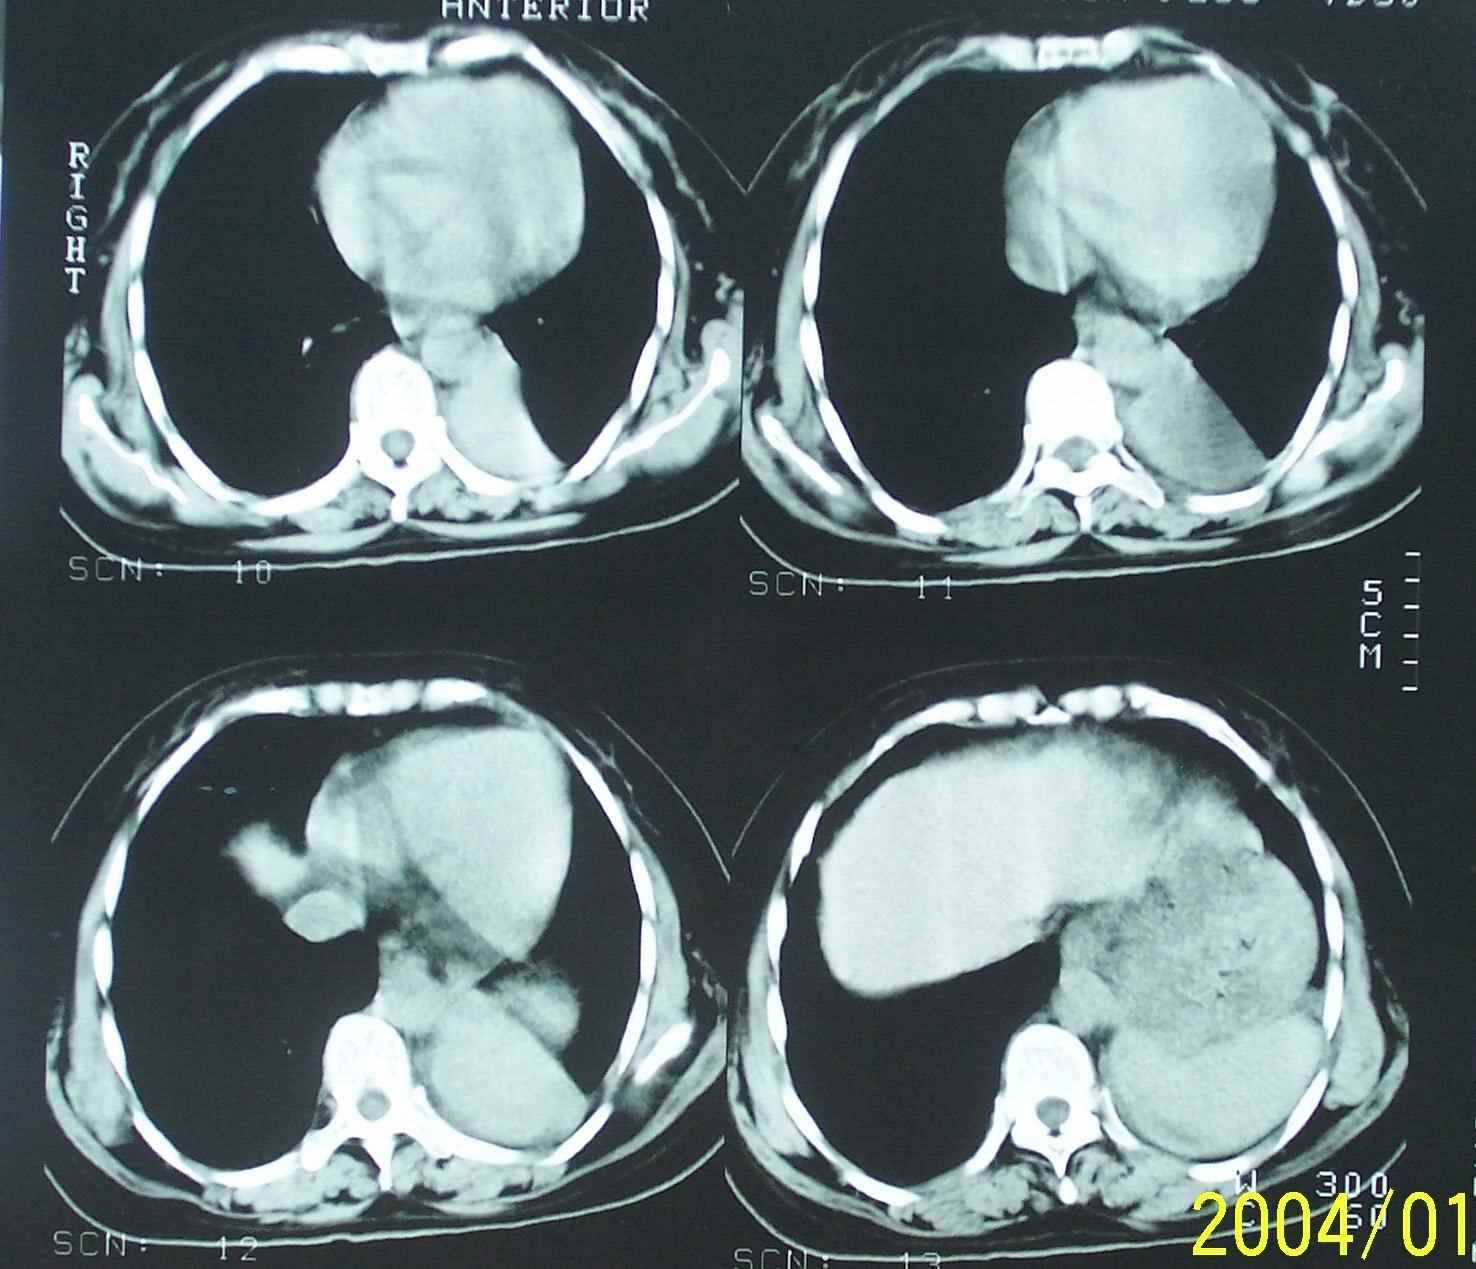

53岁女性,间断性腰部困疼、乏力一年,活动时加重。

2.左下肺病灶密度太过均匀,边缘过于光整锐利,位置特殊,其次应该考虑隔离肺的可能。

3.连续观察不能完全否定病灶是疝入胸腔的脾脏(扫描不怎么规范,跨越过大),所以膈疝也需要考虑。

应该是脾脏,因此是膈疝,

从连续观察的层面看象是疝入的脾脏

补充一下病史:三天前因咳嗽咳血检查胸片见左下肺索条状影,后复查ct